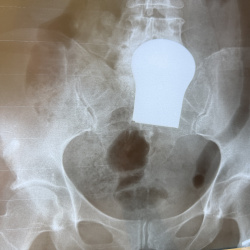

Здравствуйте,пациент с болью в колене и голеностопном суставе слева,была назначена рентгенография тазобедренных суставов,смущает нижняя ветвь лобковой кости слева,что можно поставить в диф...